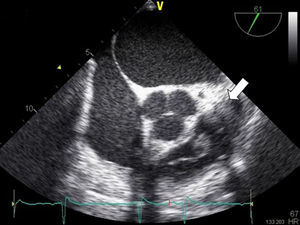

Case reportA 68-year-old man, diabetic with peripheral neuropathy, was admitted to the Internal Medicine ward due to prolonged fever. He reported suffering from both asthenia and fever over the preceding three weeks. He had been given empirical amoxicillin plus clavulanic acid two weeks previously, a treatment that led to transient symptomatic improvement. During initial observation the patient was normotensive with an axillary temperature of 37.6°C. Both cardiac and pulmonary examinations were normal. His right hallux exhibited a lesion, which by his account had been present for the preceding twelve months (Figure 1). Blood tests revealed leukocytosis – 22.70×109/l with 95.8% neutrophils – and elevated CRP (2.14mg/dl). PA chest X-rays were normal. Blood cultures revealed methicillin-susceptible Staphylococcus aureus (MSSA). Transthoracic echocardiography (TTE), and later transesophageal echocardiography (TEE), both revealed a mobile, ovoid, 1-cm diameter mass adhering to the arterial face of the pulmonary valve, and another highly mobile filiform mass also adhering to the PV and protruding into the right ventricle (Figures 2 and 3) without causing any obstruction. Taking into account the antibiotic susceptibility test results, the prescribed antibiotic therapy consisted of flucloxacillin 1000mg IV every 4h and gentamicin 1mg/kg every 8h for six weeks. The fever began to subside on the eighth day. Control echocardiography during hospitalization showed only mild to moderate pulmonary regurgitation. The patient had no other clinical manifestations or identifiable complications, including thromboembolism. Blood cultures were negative after the antibiotic course was completed. The patient was discharged home after six weeks. Nevertheless, the pre-discharge echocardiogram revealed persistence of the vegetations (Figure 4), which had developed a fibrotic appearance, and persistent mild to moderate pulmonary regurgitation.